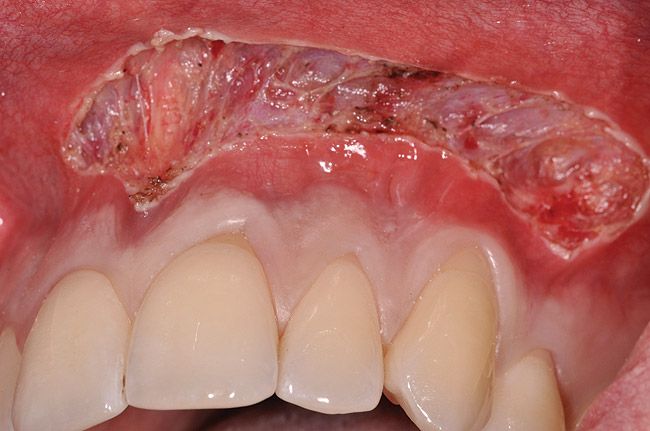

After administration of an appropriate local anesthetic, a laser-assisted split-thickness vestibuloplasty was performed superior to the mucogingival junction from the right central incisor to the left first premolar region (Figure 7). Prior to any incisions being performed, a 20-mm x 40-mm dermal matrix graft (Puros Dermis), a 0.8-mm to 1.7-mm thick piece of tissue, was trimmed to appropriate length and width to correct the gingival defect present (Figure 8). The tissue graft was sized to 6 mm in height and spanned to the mesial line angle of the left central incisor to the distal line angle of the left canine area. The dermal matrix graft was rehydrated with the patient’s own platelet-rich plasma solution, which was harvested from 20 cc of whole blood collected immediately prior to the surgical procedure (Figure 9).

Fig 7. Laser-assisted split-thickness vestibuloplasty performed.

Figure 7